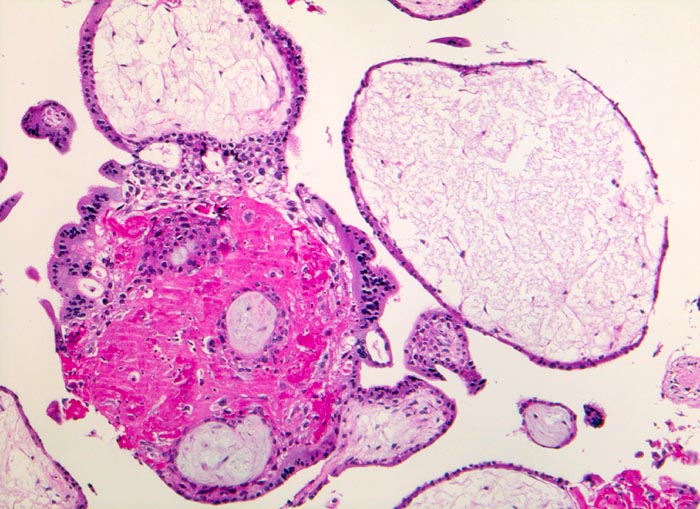

Abortkurettage: Retentionszeichen

Regressiv veränderte Plazentarzotten mit hydropisch geschwollenem und degeneriertem Stroma. Fibrinablagerungen zwischen den Zotten.

Missed abortion in der 11. Schwangerschaftswoche, sonographisch entsprechend der 9. Schwangerschaftswoche.

Oftmals wird ein Frühabort nicht sofort bemerkt. Je nach Zeitdauer, die zwischen Absterben der Frucht und Kurettage verstreicht, finden sich unterschiedlich ausgeprägte Retentionszeichen im Abortmaterial. Die degenerativen Veränderungen können die Interpretation der morphologischen Befunde am chorialen Gewebe erschweren, zumal abortverursachende Zirkulationsstörungen ähnlich aussehen können.